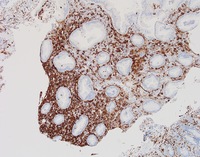

CD56 stain

CD56 is strongly positive as is typical of most NK-cell proliferations. Additionally CD4 and CD8 were negative while EBV was negative.

NKcell-enteropathyCD56

#00061921

#00061920